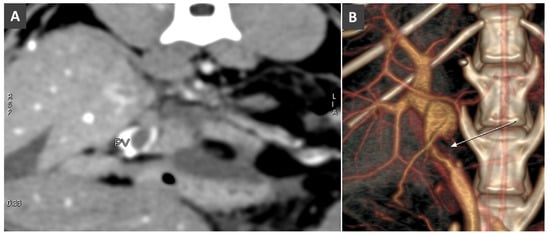

Congenital Portosystemic Shunt

- Lamb, C.R.; White, R.N. Morphology of congenital intrahepatic portacaval shunts in dogs and cats. Vet. Rec. 1998, 142, 55–60. [Google Scholar] [CrossRef]

- White, R.N.; Burton, C.A. Anatomy of the patent ductus venosus in the dog. Vet. Rec. 2000, 146, 425–429. [Google Scholar] [CrossRef]